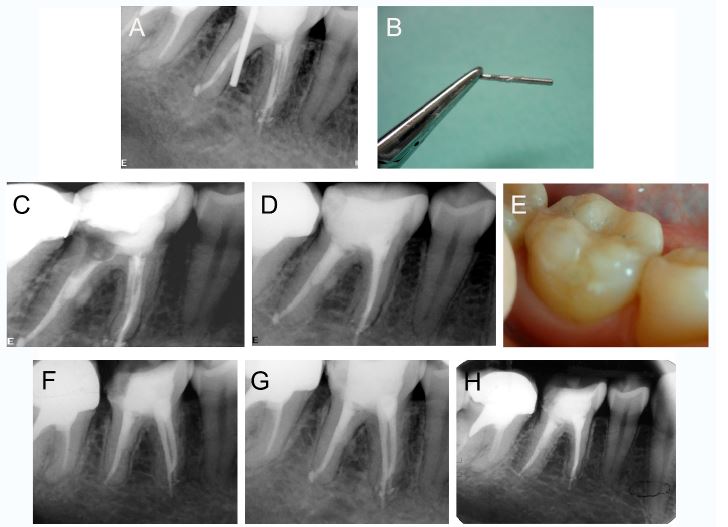

An asymptomatic 25-year-old female patient was referred to the endodontics department to evaluate the right mandibular first molar (FDI tooth number 46). The medical history of the patient was non- contributory. The dental history included a recent root canal treatment and post placement in the affected tooth. The clinical examination showed that there were no sensitivity to percussion or palpation and no extraoral or intraoral swelling. The radiographic examination revealed a radiopaque element in the distal root, which was compatible with metal post, perforating the middle third of the root. The diagnosis was “previously treated" and “normal periapical tissues". The treatment alternatives were discussed together with the patient, who consented to perform the removal of the metal post followed by sealing of perforation and replacement of restoration.

The local anesthesia was administered by oral infiltration of 2% lidocaine with 1: 100,000 adrenaline (Alphacaine, Rio de Janeiro, RJ, Brazil). Then, rubber dam isolation was performed, the previous restoration was removed, the access was obtained, and the metal post was removed using an ultrasonic tip (E12, Helse Ultrasonic, Santa Rosa de Viterbo, SP, Brazil) coupled to an ultrasonic device (MiniEndo, Kerr Endodontics, Brea, CA, USA). A non-bleeding large perforation, with approximately 2-3mm in diameter, was identified in the middle third of the distal root. Before sealing, irrigation with 2% chlorhexidine (Maquira, Maringa, PR, Brazil) was performed using a 27G side-vented needle (Endo-Eze Irrigator Tip, Ultradent Products, South Jordan, UT, USA). After drying the perforation site with paper points, a matrix of calcium sulfate mixed with distilled water was placed, which acted as a barrier between bone and tooth. Once set the matrix after approximately 1 minute, the white MTA Angelus (Angelus, Londrina, PR, Brazil) repair cement was placed using an MTA Applicator (Angelus). After 24 h, the cervical and middle thirds of the distal canal were obturated using gutta-percha and AH Plus sealer (Dentsply DeTrey, Konstanz, Germany) using the continuous wave technique. The access cavity was sealed with a glass ionomer cement (Fuji IX GP Fast; GC Corporation, Tokyo, Japan). An indirect resin restoration was placed after adjustment of occlusion and proximal contacts. The 1-month, 1-year and 3-year follow-up showed favorable evolution (figure 1).